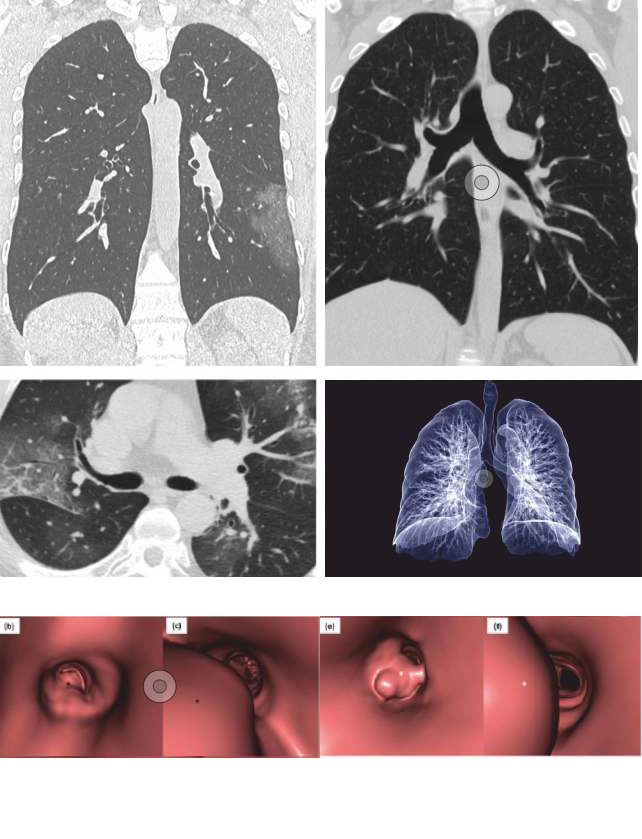

HRCT Chest Images

VRT Images

CT Angiography Images